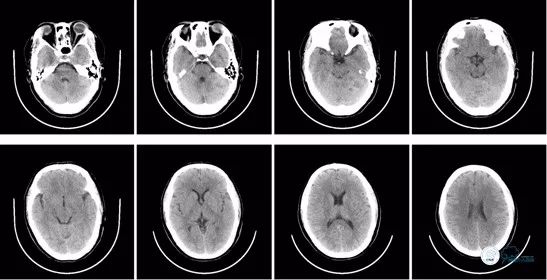

入院时急查头颅CT示:颅脑未见明显异常。ASPECT评分10分。

入院时急诊头颅CT:

图1

术后即刻头颅CT:可见少量造影剂渗出,排除术后出血。

术后8小时头颅CT:

图13